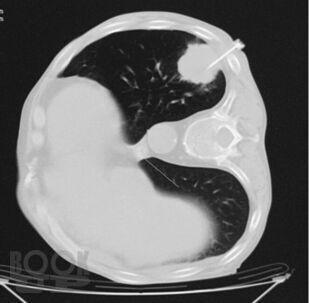

Учебное пособие основано на современных данных по диагностике и лечению рака легкого. Оно содержит информацию об эпидемиологии, этиологии, клинических проявлениях и профилактике заболевания.

В издании изложены сведения о современных методах исследования, применяемых для диагностики, оценки стадии заболевания с учетом Международной классификации по системе TNM и выбора оптимального метода лечения.